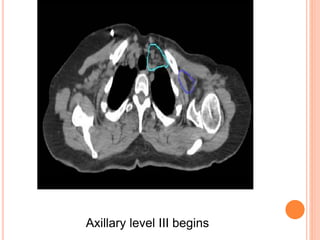

REGIONAL NODAL CONTOURING

SCF begins

Axillary level III begins

Axillary level II begins

Axillary level I begins

Axillary level I ends

IMC begins

IMC ends